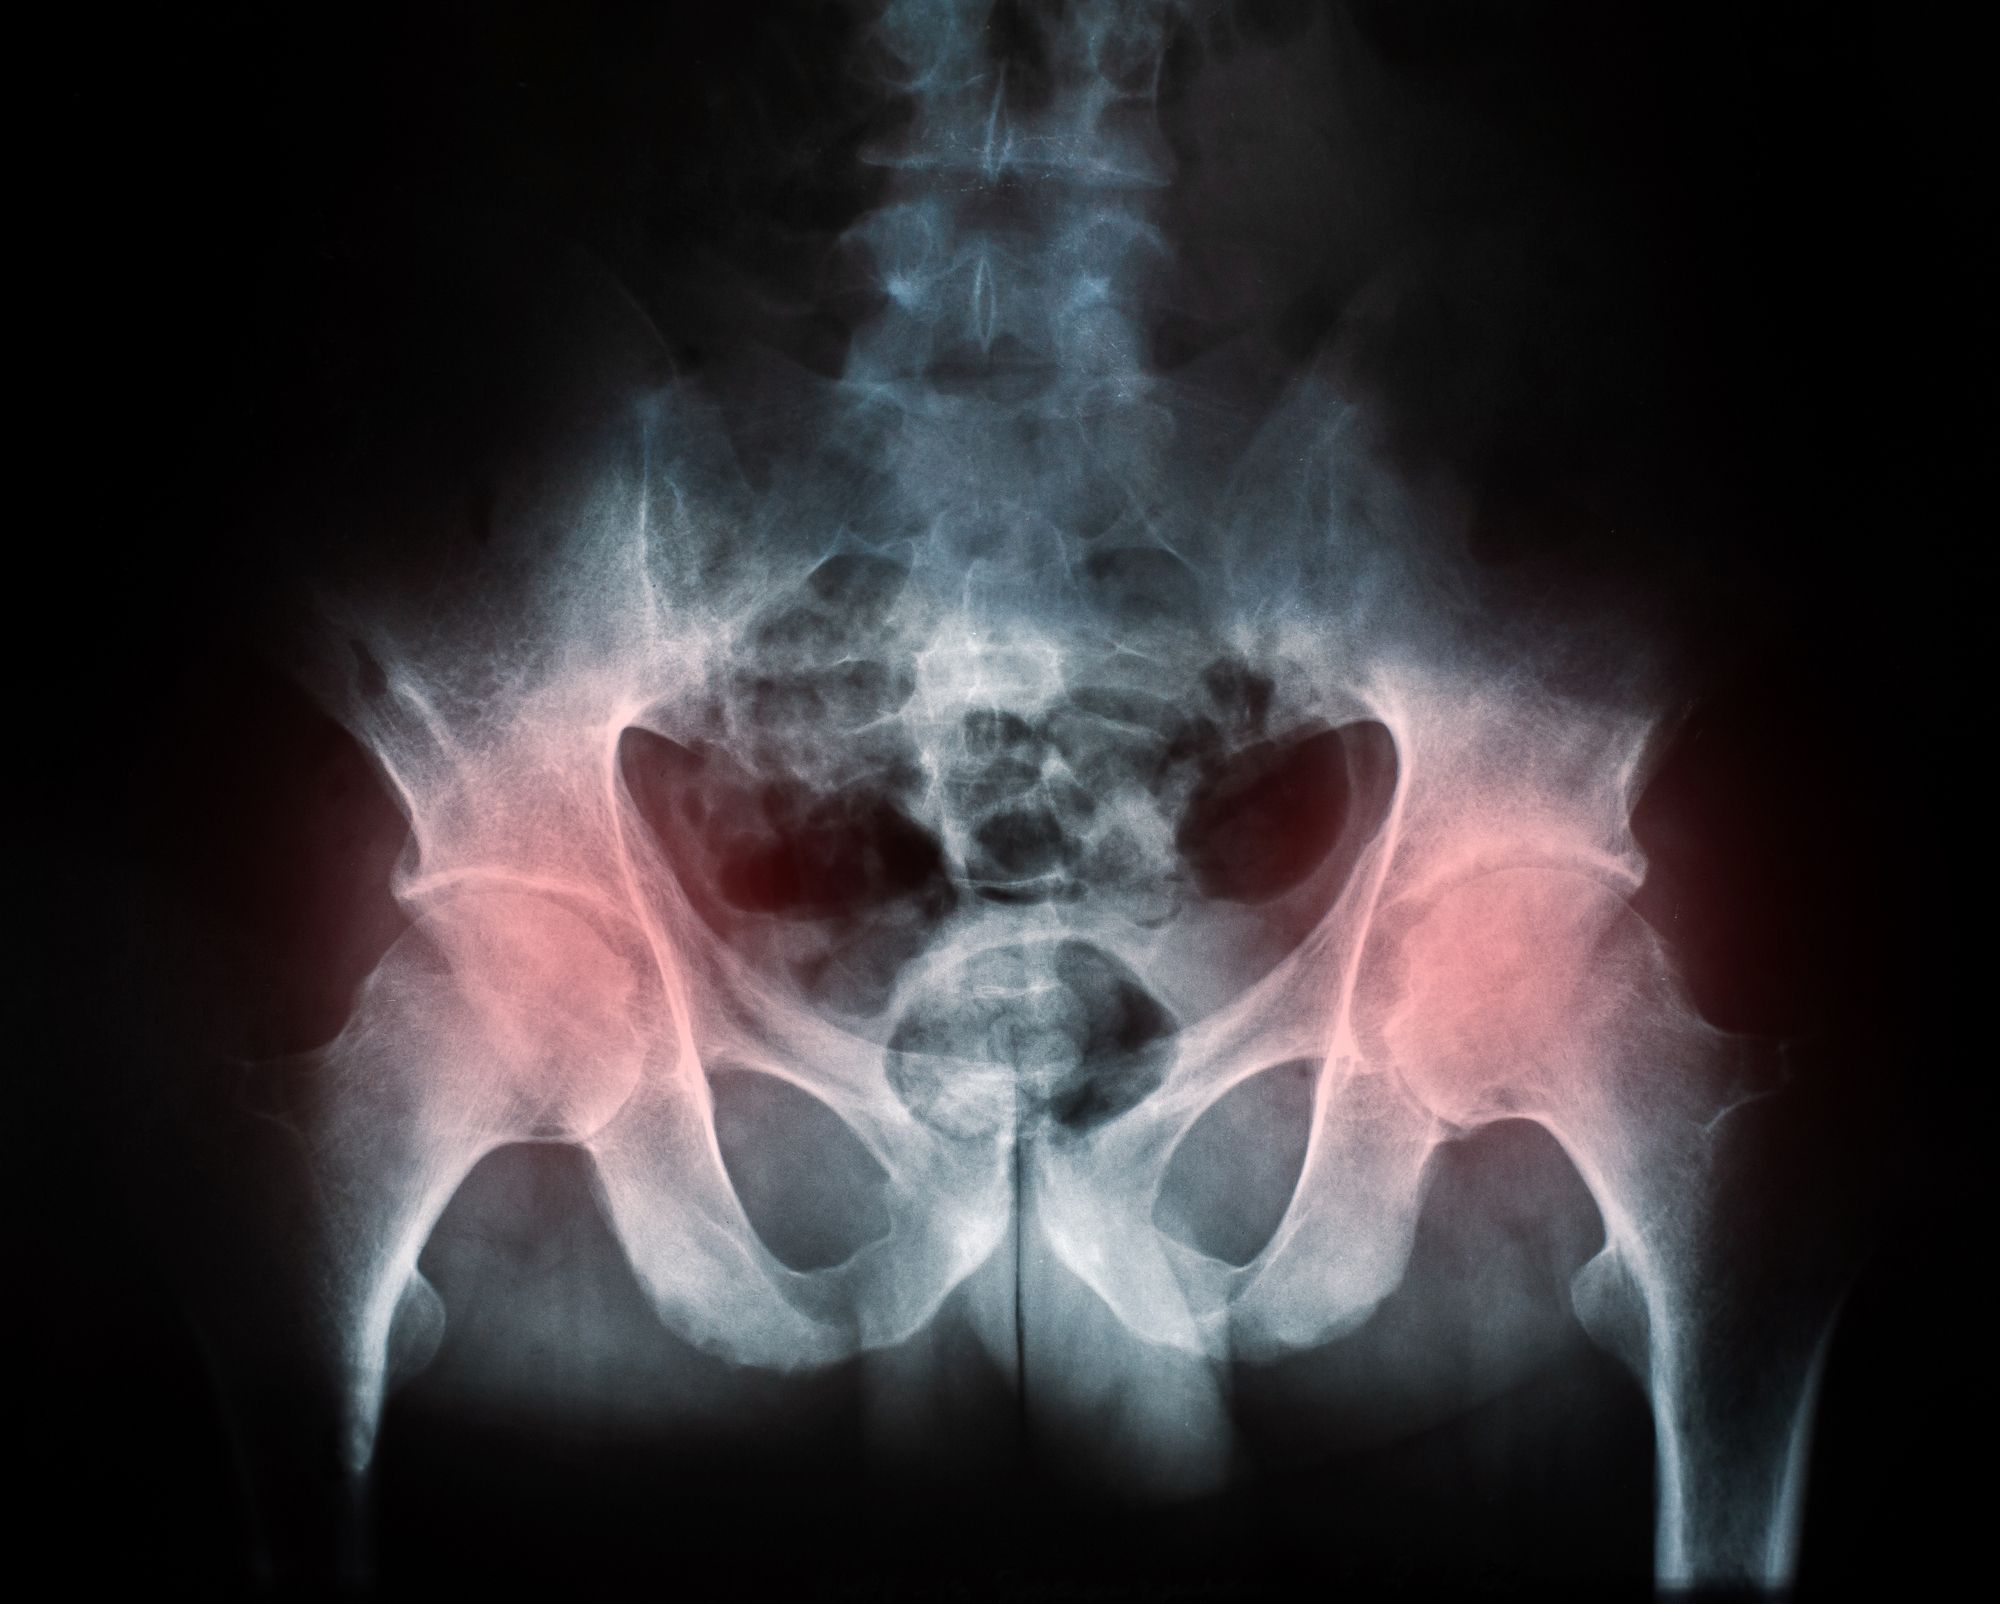

DePuy Zimmer hip implant hip replacementMedical device manufacturers are supposed to design products that do not lead to metal on metal hip implant failures. Their ultimate goal, however, is to make money for their stockholders. In a sign that the cases brought by Zimmer hip implant failure lawsuit lawyers are having an effect, the company failed to hit its own targets.

In one recent case filed by a Zimmer metal hip implant failure lawsuit lawyer, a surgeon trying to repair damage found that the cup near the pelvis was actually able to spin around multiple times. It only took him a few taps. In this and similar cases, multiple procedures are required to completely remove the metal on metal hip implants.

Unfortunately, that is not even always possible, leading to ongoing pain and suffering. Even when Zimmer hip implant failure revision surgeries do work, metals can leach into the body. This affects the circulatory system and can cause infections and cognitive dysfunction.